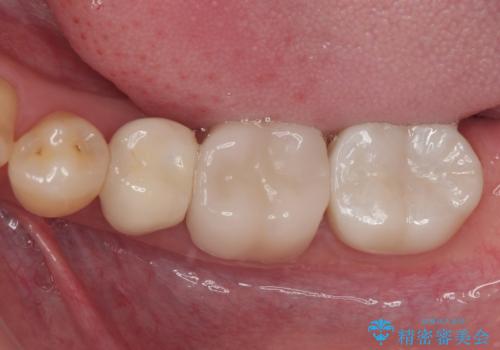

部分的な詰め物ですと、再度破損リスクが高いため、高強度のセラミッククラウンにて補綴治療を行うこととしました。

治療から9か月ほどが経過した時点で、違和感や痛みはなく、歯根端切除術を行った右下は、レントゲンでも良好な経過が確認できました。

今後も継続して観察を行っていくこととなります。